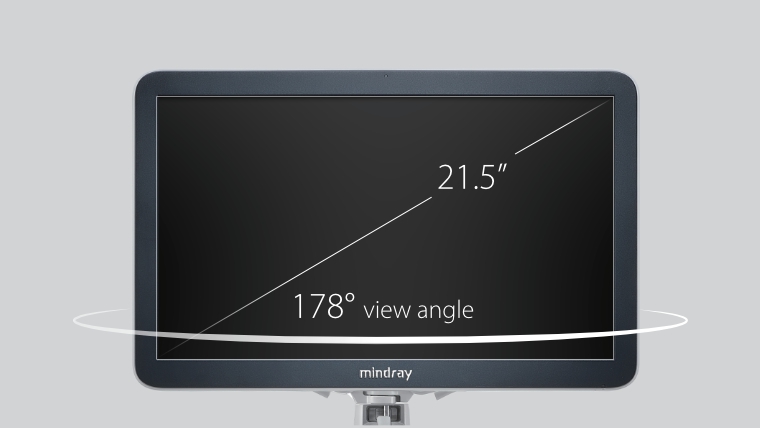

eXceeding Experience

Experiencia con alta productividad